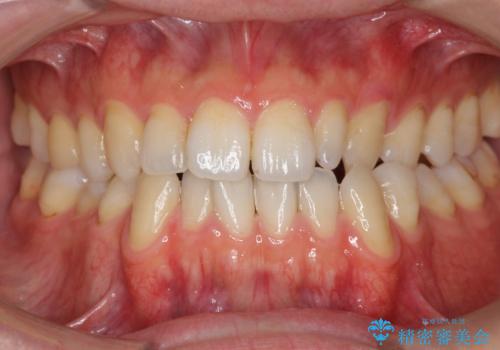

前歯の矮小歯 奥歯の反対咬合 をインビザラインで

- 上下の前歯が気になり来院。

左上2が矮小歯で小さく、また、左の奥歯が反対咬合になっていました。

左上2番はセラミッククラウンで反対側と同じ大きさにしました。

インビザラインでの臼歯の反対咬合の治療は難しいことが多いです。

今回は下の前歯を1本抜くことで、下の奥歯をしっかり内側に傾けて治療を行いました。